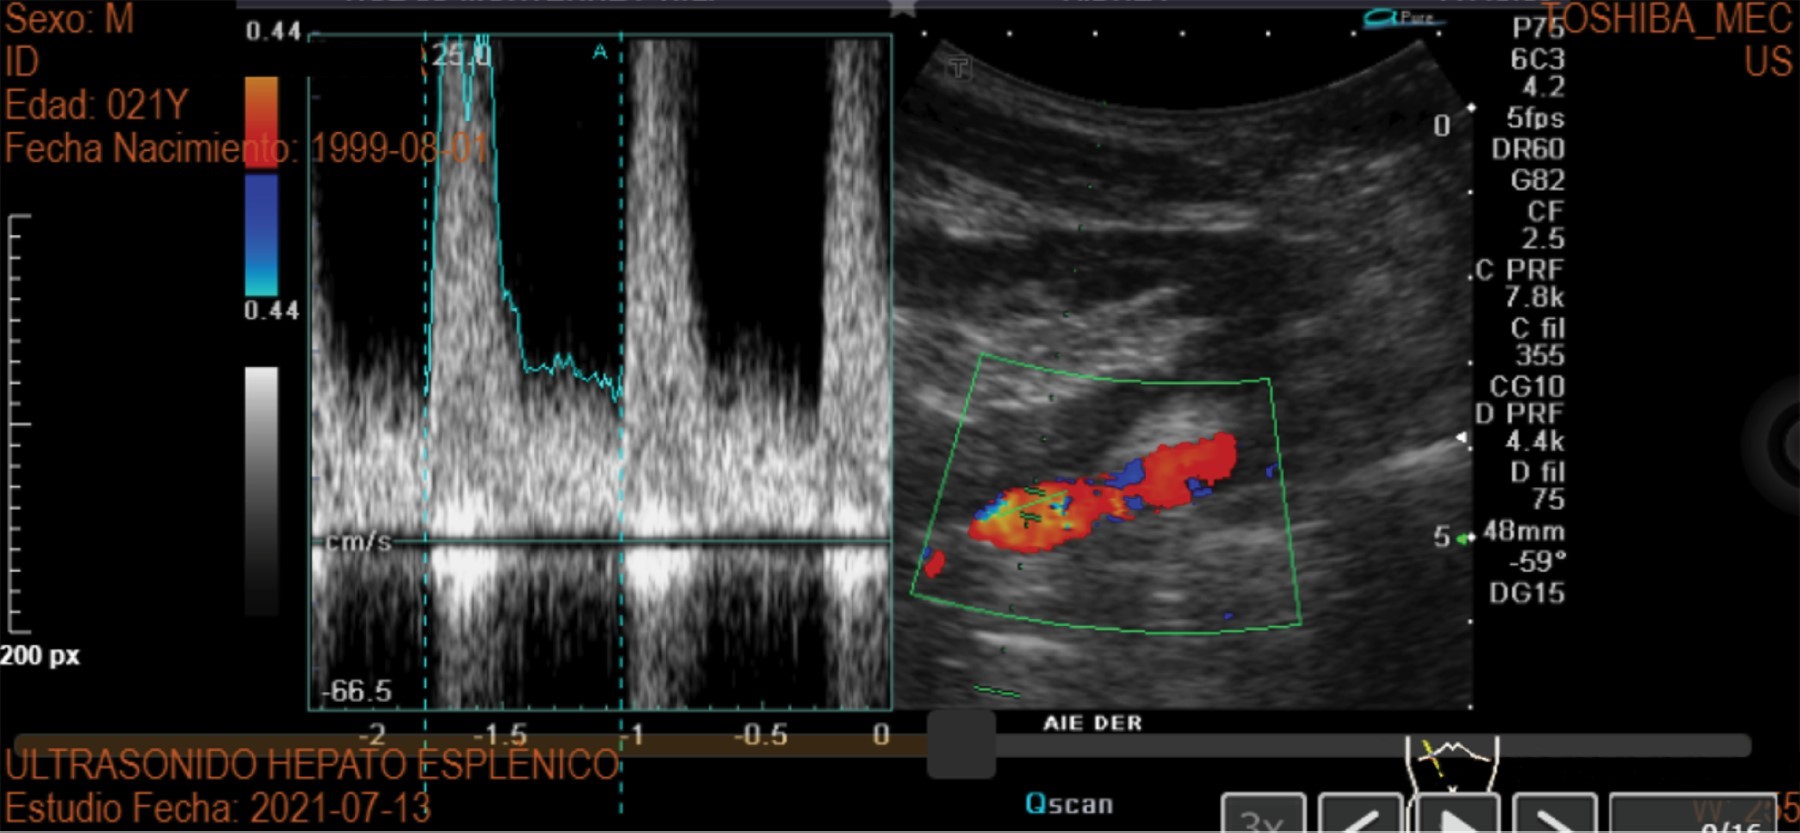

Figure 2